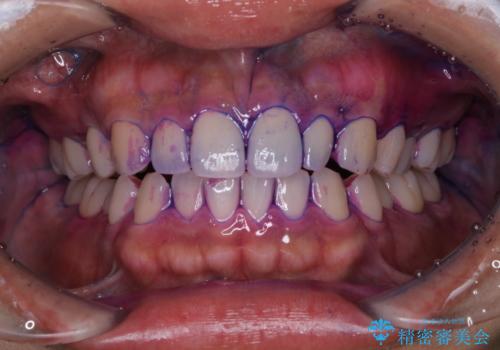

ホワイトニング前にクリーニング

- ご自身でのホームホワイトニングをする前に、綺麗にクリーニングをして欲しいとのことで来院されました。

今後、ホームホワイトニング予定との事で、クリーニングPMTC(保険適応外)60分コースを行いました。汚れを取り除き、ご自身の本来の歯の表面になることでツヤがでます。

歯の表面に汚れがついたままホワイトニングを行うと、ホワイトニングの効果が出づらいことがあります。

ホワイトニングご希望の場合は、まずクリーニングを行うことをおすすめします。